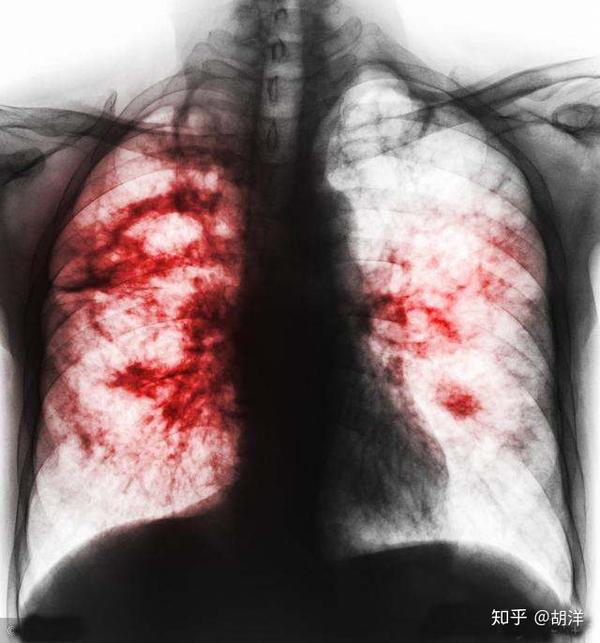

读图诊断:肺癌的临床表现,你知道吗?

肺癌的晚期症状介绍